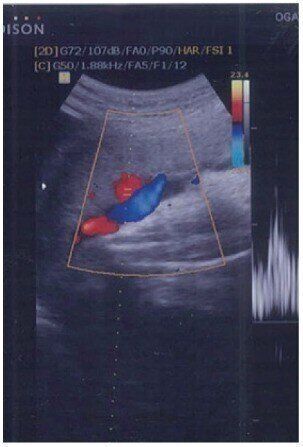

血液の流れがわかる!精密検査をするためのカラー超音波

2Dで検査をして異常があったときに、詳しい診断ができます。フルカラーではなく、大部分は白と黒なので、2Dとあまり変わりませんが、いちばんの違いは血液の流れをカラーで写し出すことです。心臓や脳内、へその緒の中の血流の状態をチェックします。